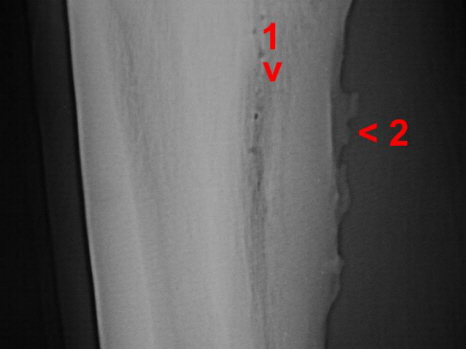

Knochenwucherung u. Verwachsung Griffelbein